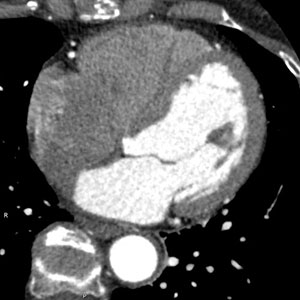

特に、従来、心臓カテーテル検査のみにて描出が可能であった冠動脈を、近年では非侵襲的にCTで評価することができるようになりました(図3)。冠動脈病変は、心筋梗塞症や狭心症の原因となるため、その評価は大変重要です。この他、大動脈瘤などの大動脈疾患や、心臓腫瘍・血栓の有無などの評価もできます。また、CT機器の進歩により、現在は患者さんが受ける被ばく線量の低減や、造影剤投与量の減量も可能となりました。

• 図3:心臓CT 左冠動脈前下行枝